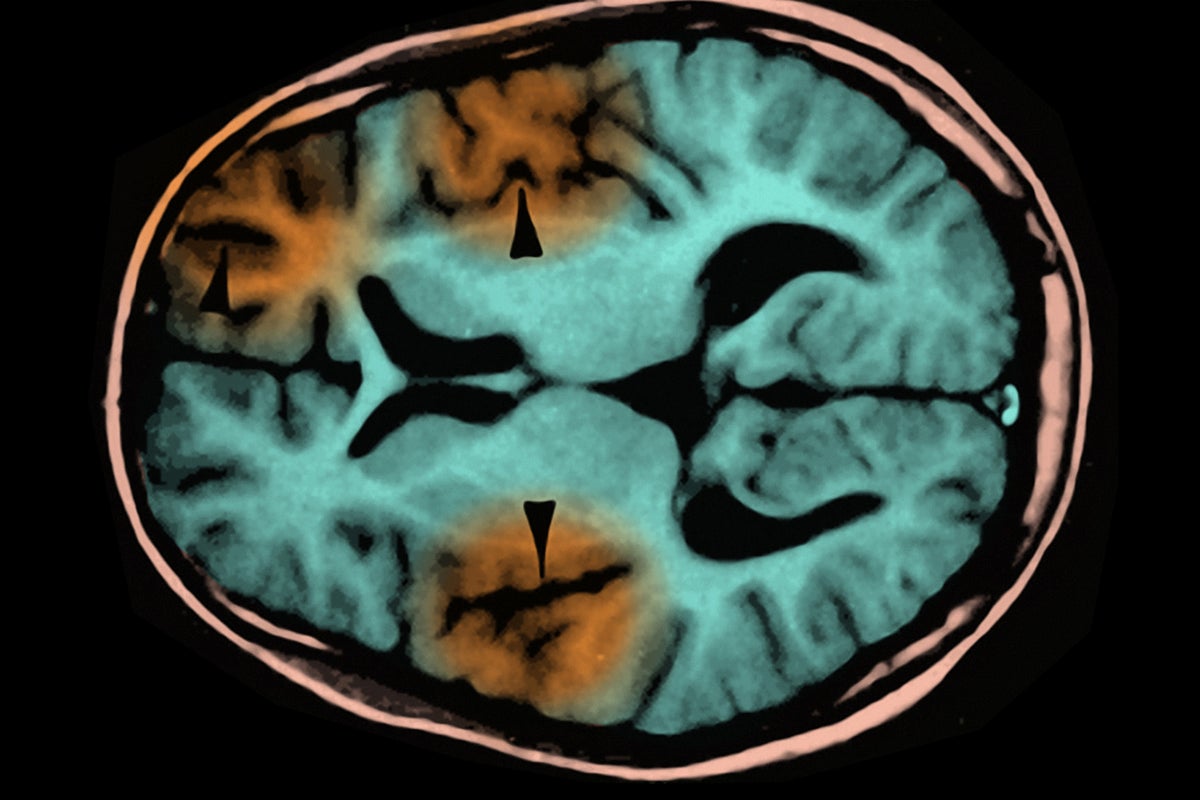

Subacute sclerosing panencephalitis is a progressive neurological condition characterized by the deterioration of cognitive and motor functions. While SSPE is rare, affecting approximately four to eleven individuals for every 100,000 cases of measles, its impact is devastating. The mortality rate for SSPE stands at an alarming 95%, and currently, there is no known cure. This grim statistic underscores the importance of immunization against measles, particularly for children who represent the most vulnerable demographic.

The recent death of a child from SSPE should serve as a stark reminder of the potential dangers posed by measles. The disease can lead to serious health complications—it is not merely a rash and fever. Measles can cause pneumonia, encephalitis, and in rare cases, SSPE, which may not present symptoms until years after the initial illness. Parents and guardians must understand that the consequences of not vaccinating their children extend beyond individual risk; they threaten community health as well.